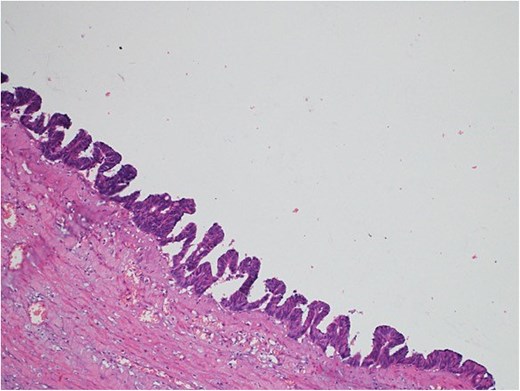

A 47-year-old male patient, with a documented history of diabetes mellitus but no previous surgical interventions, presented with right lower quadrant (RLQ) abdominal pain, which was associated with recurrent vomiting episodes (four times) within the preceding 24 h. The pain did not radiate and was not aggravated by any specific factors. The patient denied fever, urinary symptoms, and changes in bowel habits. On physical examination, he appeared well, with mild pain but no distress. Abdominal examination revealed minimal tenderness and rebound tenderness in the RLQ, but the abdomen was otherwise soft and lax, with no evidence of guarding, rigidity, or fullness. The patient’s laboratory profile was within normal ranges. Abdominal computed tomography (CT) with contrast revealed a dilated, fluid-filled appendix with a maximum diameter of 2.2 cm and tiny peripheral calcifications. There was no surrounding fat stranding or free fluid. The rest of the bowel loops were grossly unremarkable (Fig. 1). A diagnosis of appendicular mucocele was made, and the patient underwent an open appendectomy. The patient’s postoperative course remained clinically uneventful. Gross findings of the appendectomy specimen measured 6 × 2.5 × 2 cm, with a smooth outer surface and no identified perforation. Pathology examination revealed LAMN, confined to the appendix. The sections showed flat mucinous epithelium originating from the lumen, and there was no evidence of extra-appendiceal mucinous extension. The margin was negative for mucinous neoplasm (Fig. 2). A referral to the Colorectal Surgery Clinic was arranged to ensure a thorough evaluation and appropriate follow-up.

Light microscopy images of the appendix show low-grade dysplastic epithelium on the surface of the appendix (hematoxylin and eosin stain; 10×).